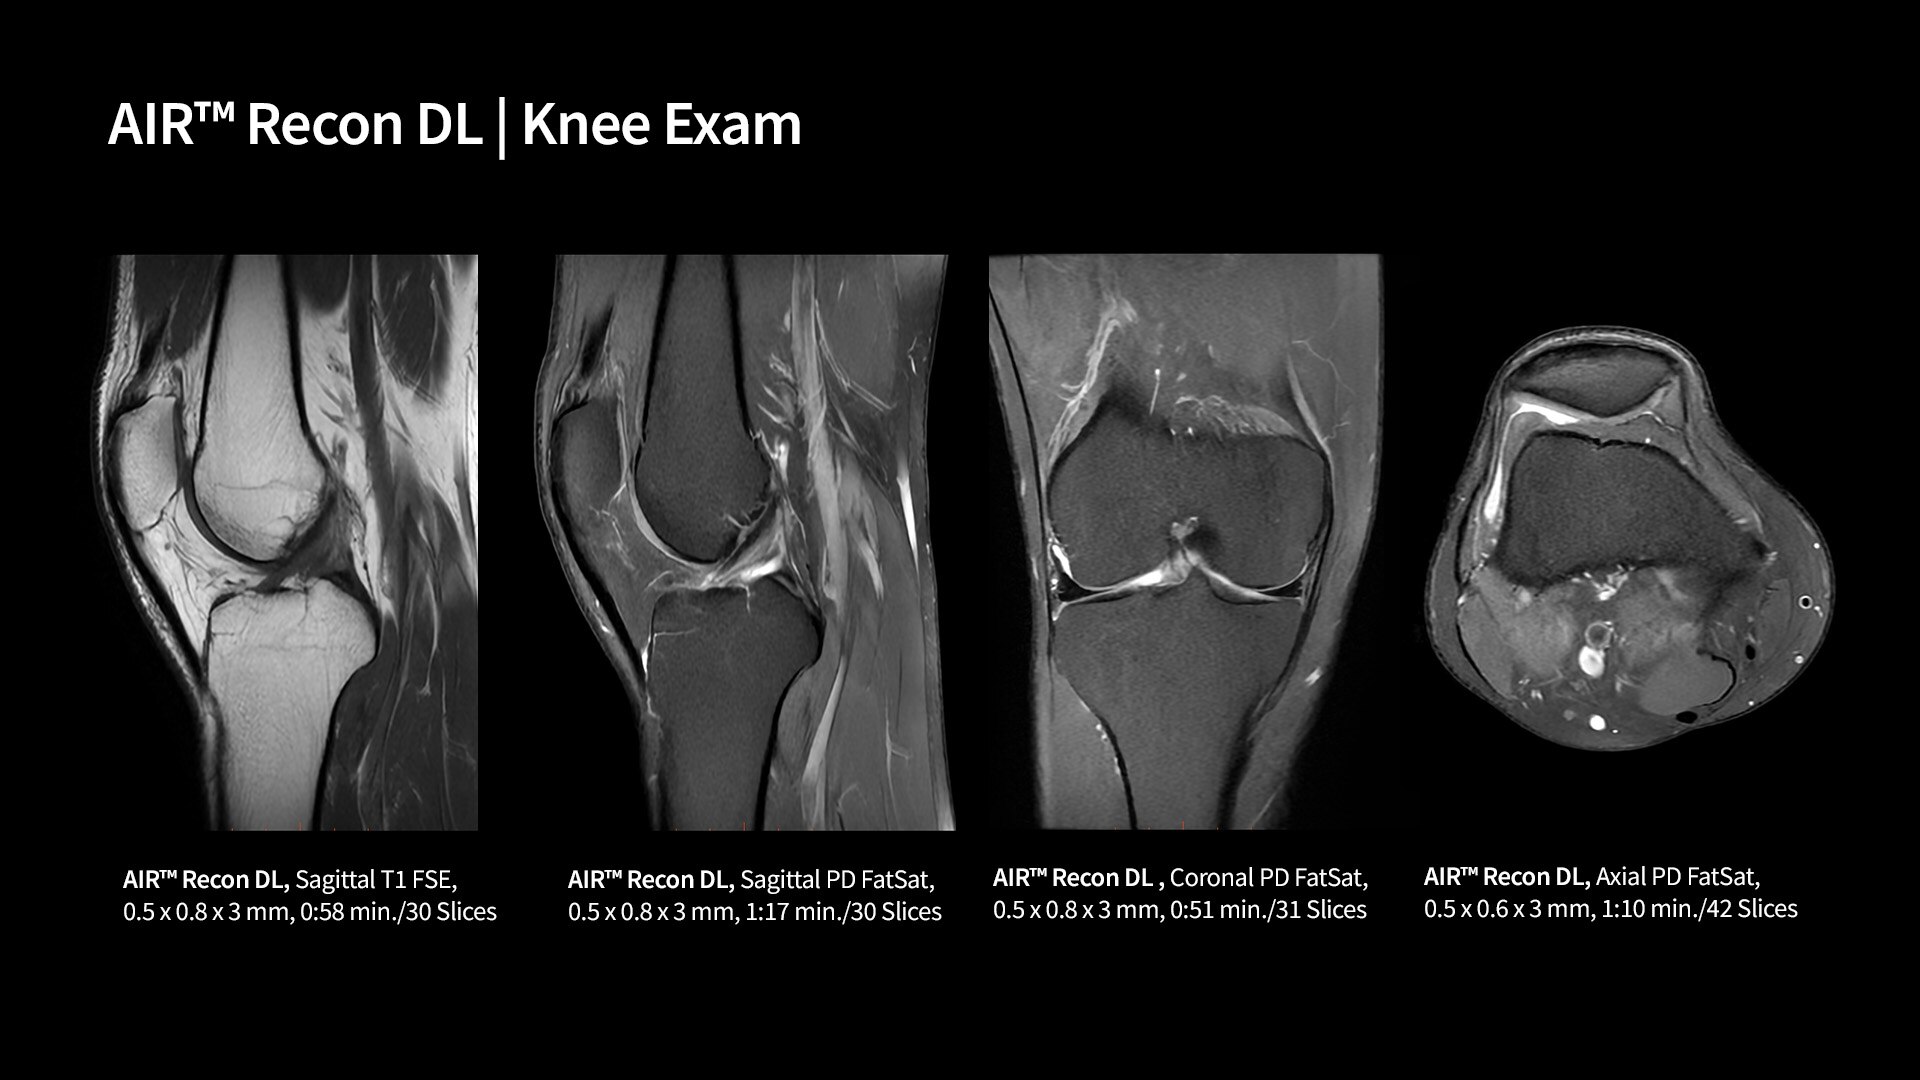

AIR™ Recon DL

AIR™ Recon DL can evolve your MRI scanner’s capabilities by creating exceptional image quality without compromising scan time.